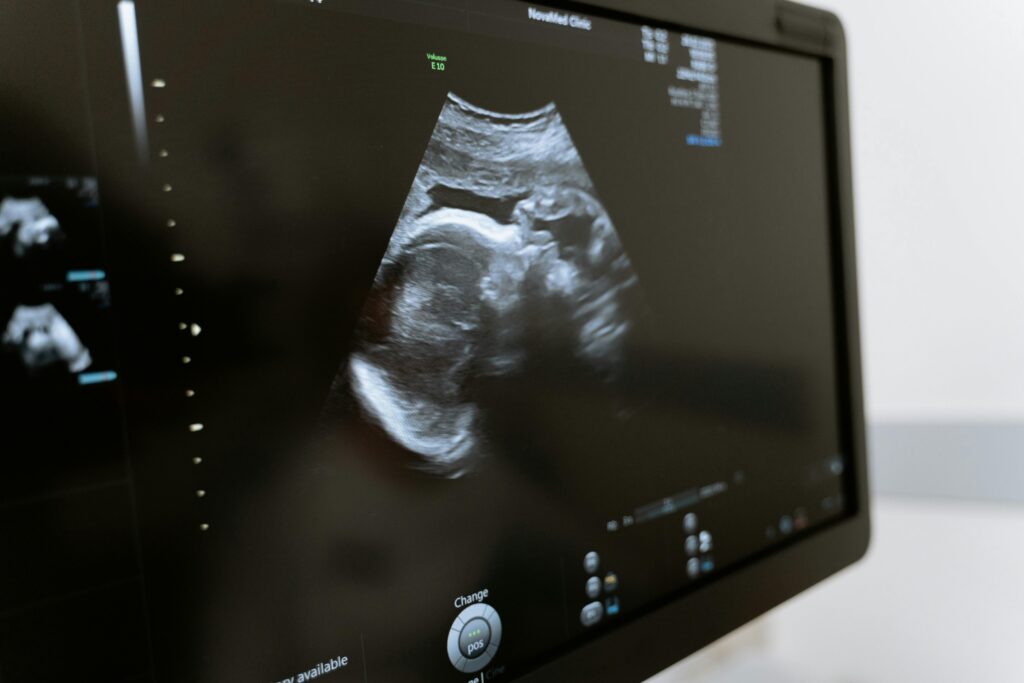

During her ultrasound, as the image appeared on the screen, there was a possibility of twins, but due to her early gestational age, staff couldn’t confirm indefinitely.

For a moment, awe overtook fear. Emily mentioned earlier that she felt like she was carrying twins. Could this be confirmation that she was meant to have her babies? But then, the weight of her heart defect and the words of her doctors pulled her back. “I’ll carry this pregnancy only if my cardiologist says it’s safe,” she said, holding onto a sliver of hope.